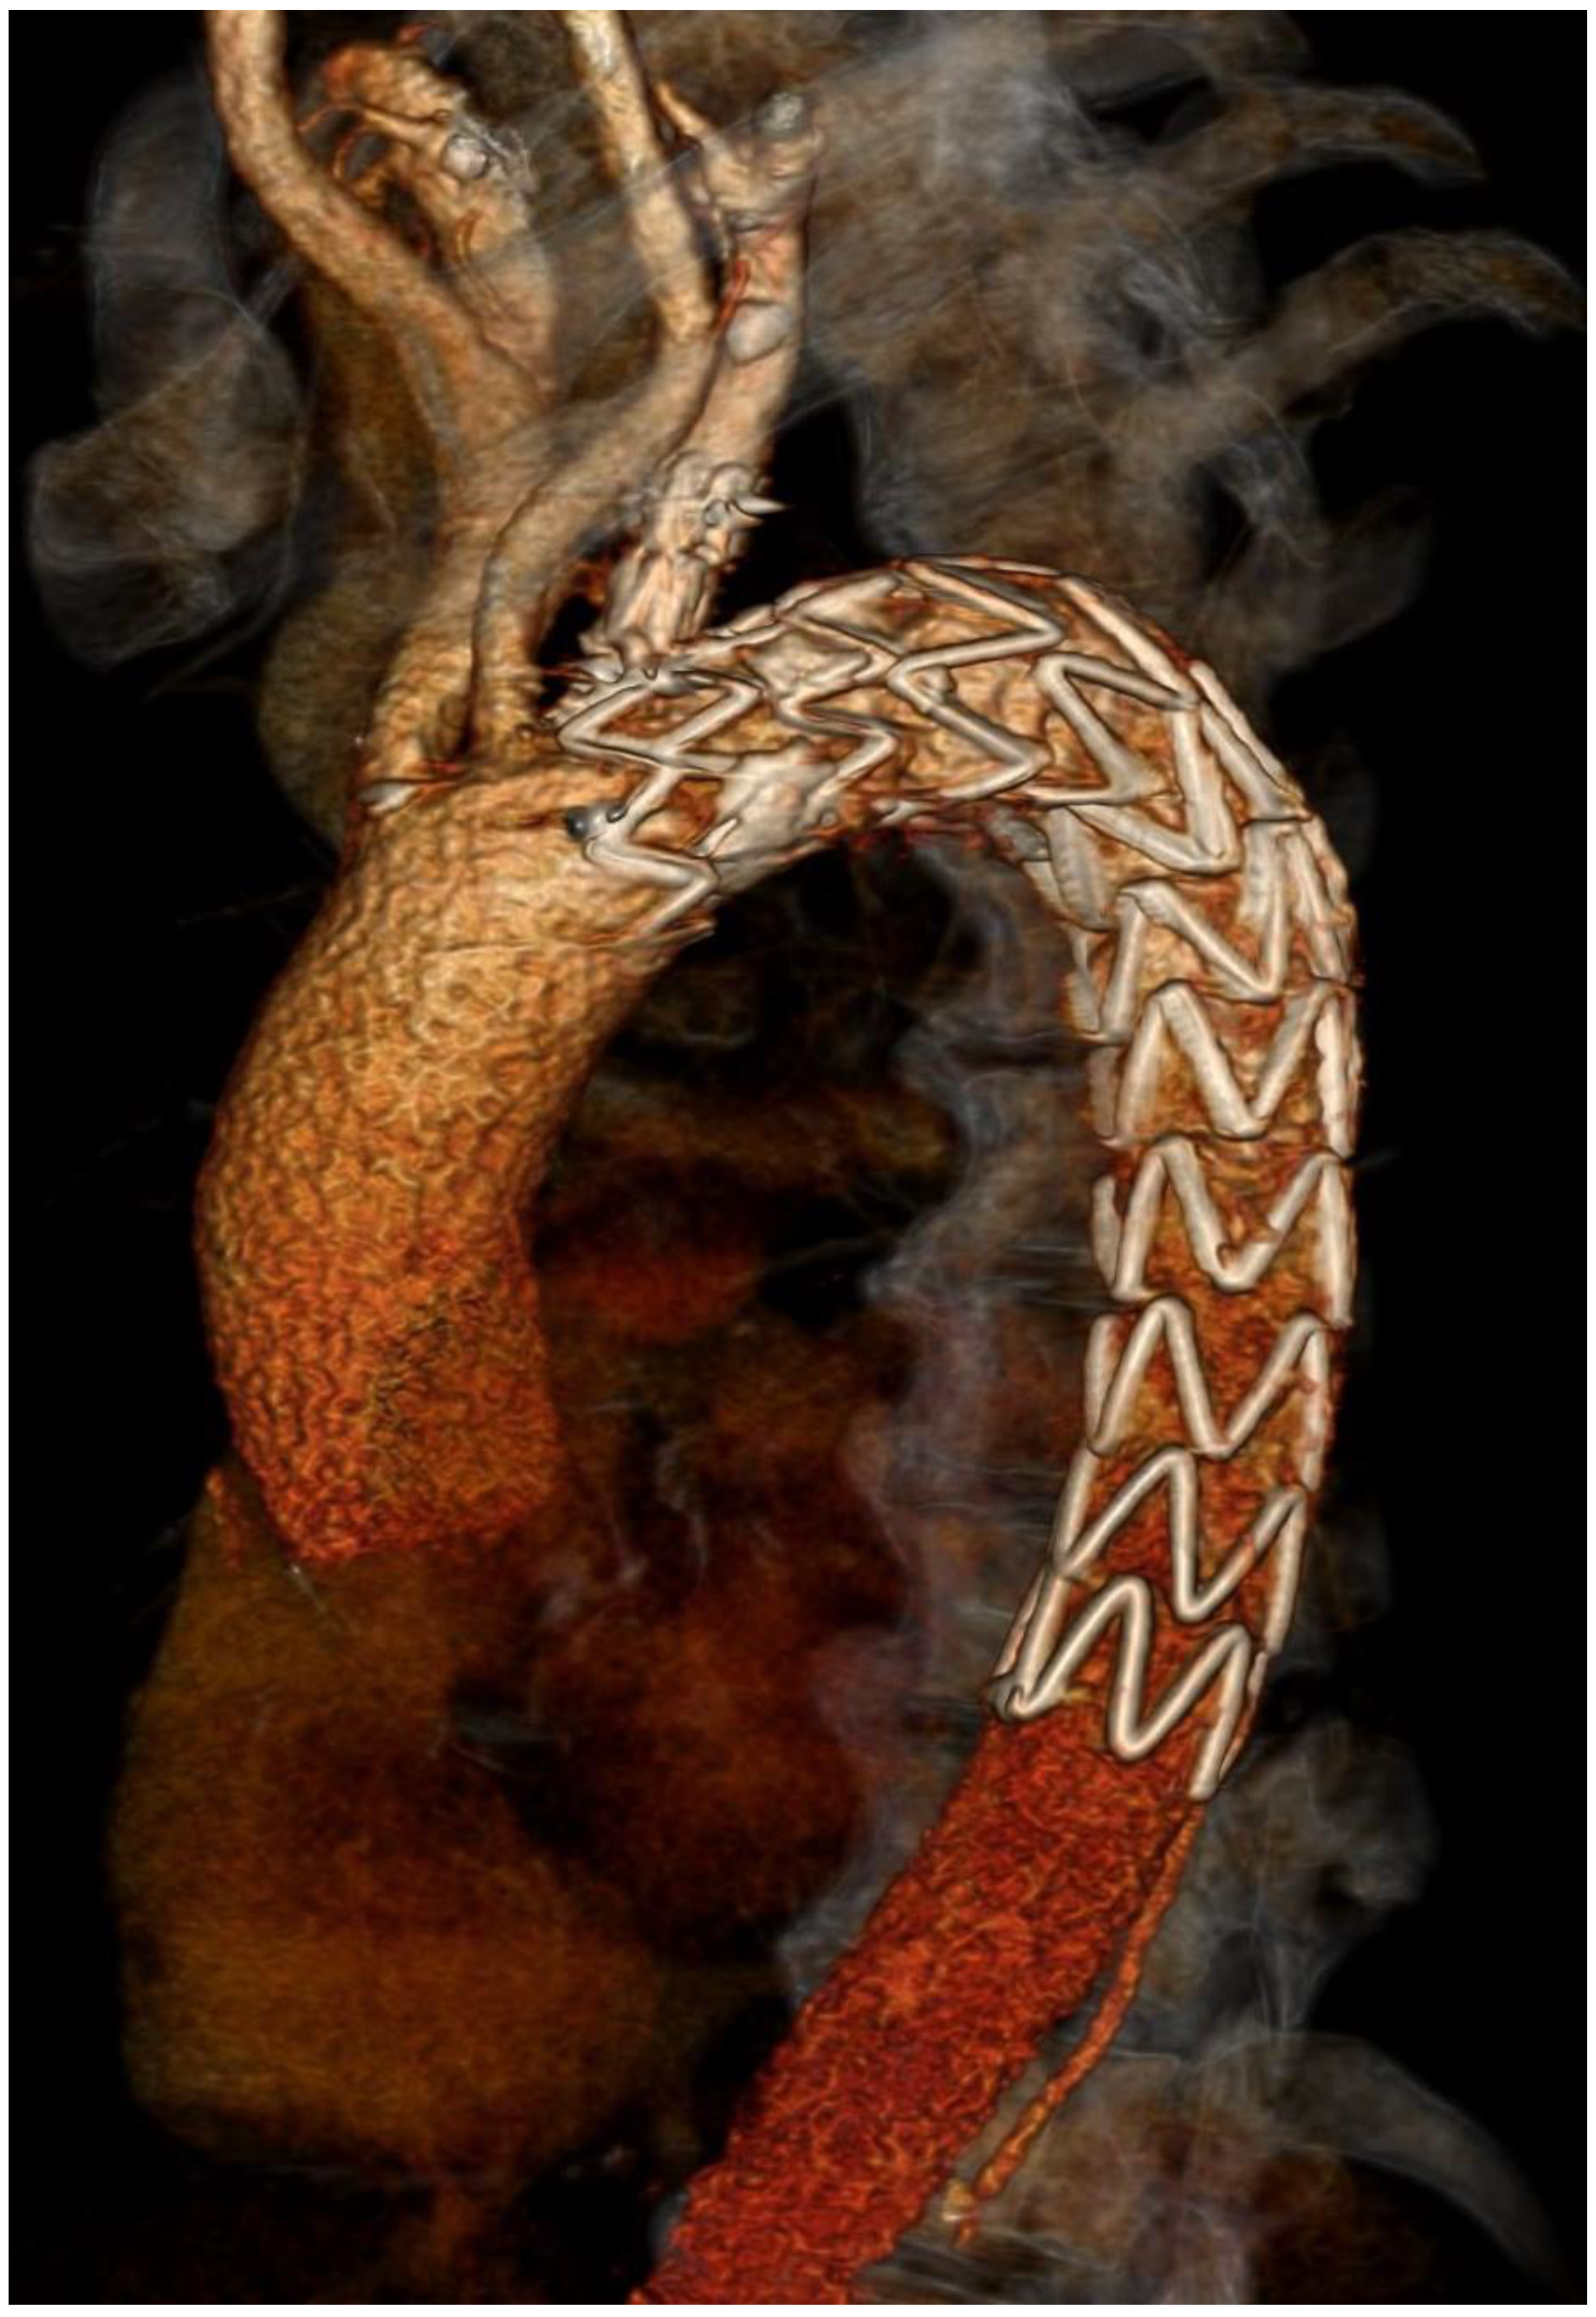

Finally, CT angiography performed after 24 h showed good results for endovascular prosthesis implantation (Figure 3 and Figure 4).

Figure 4. Postprocedural 3D CT showing Castor stent graft.